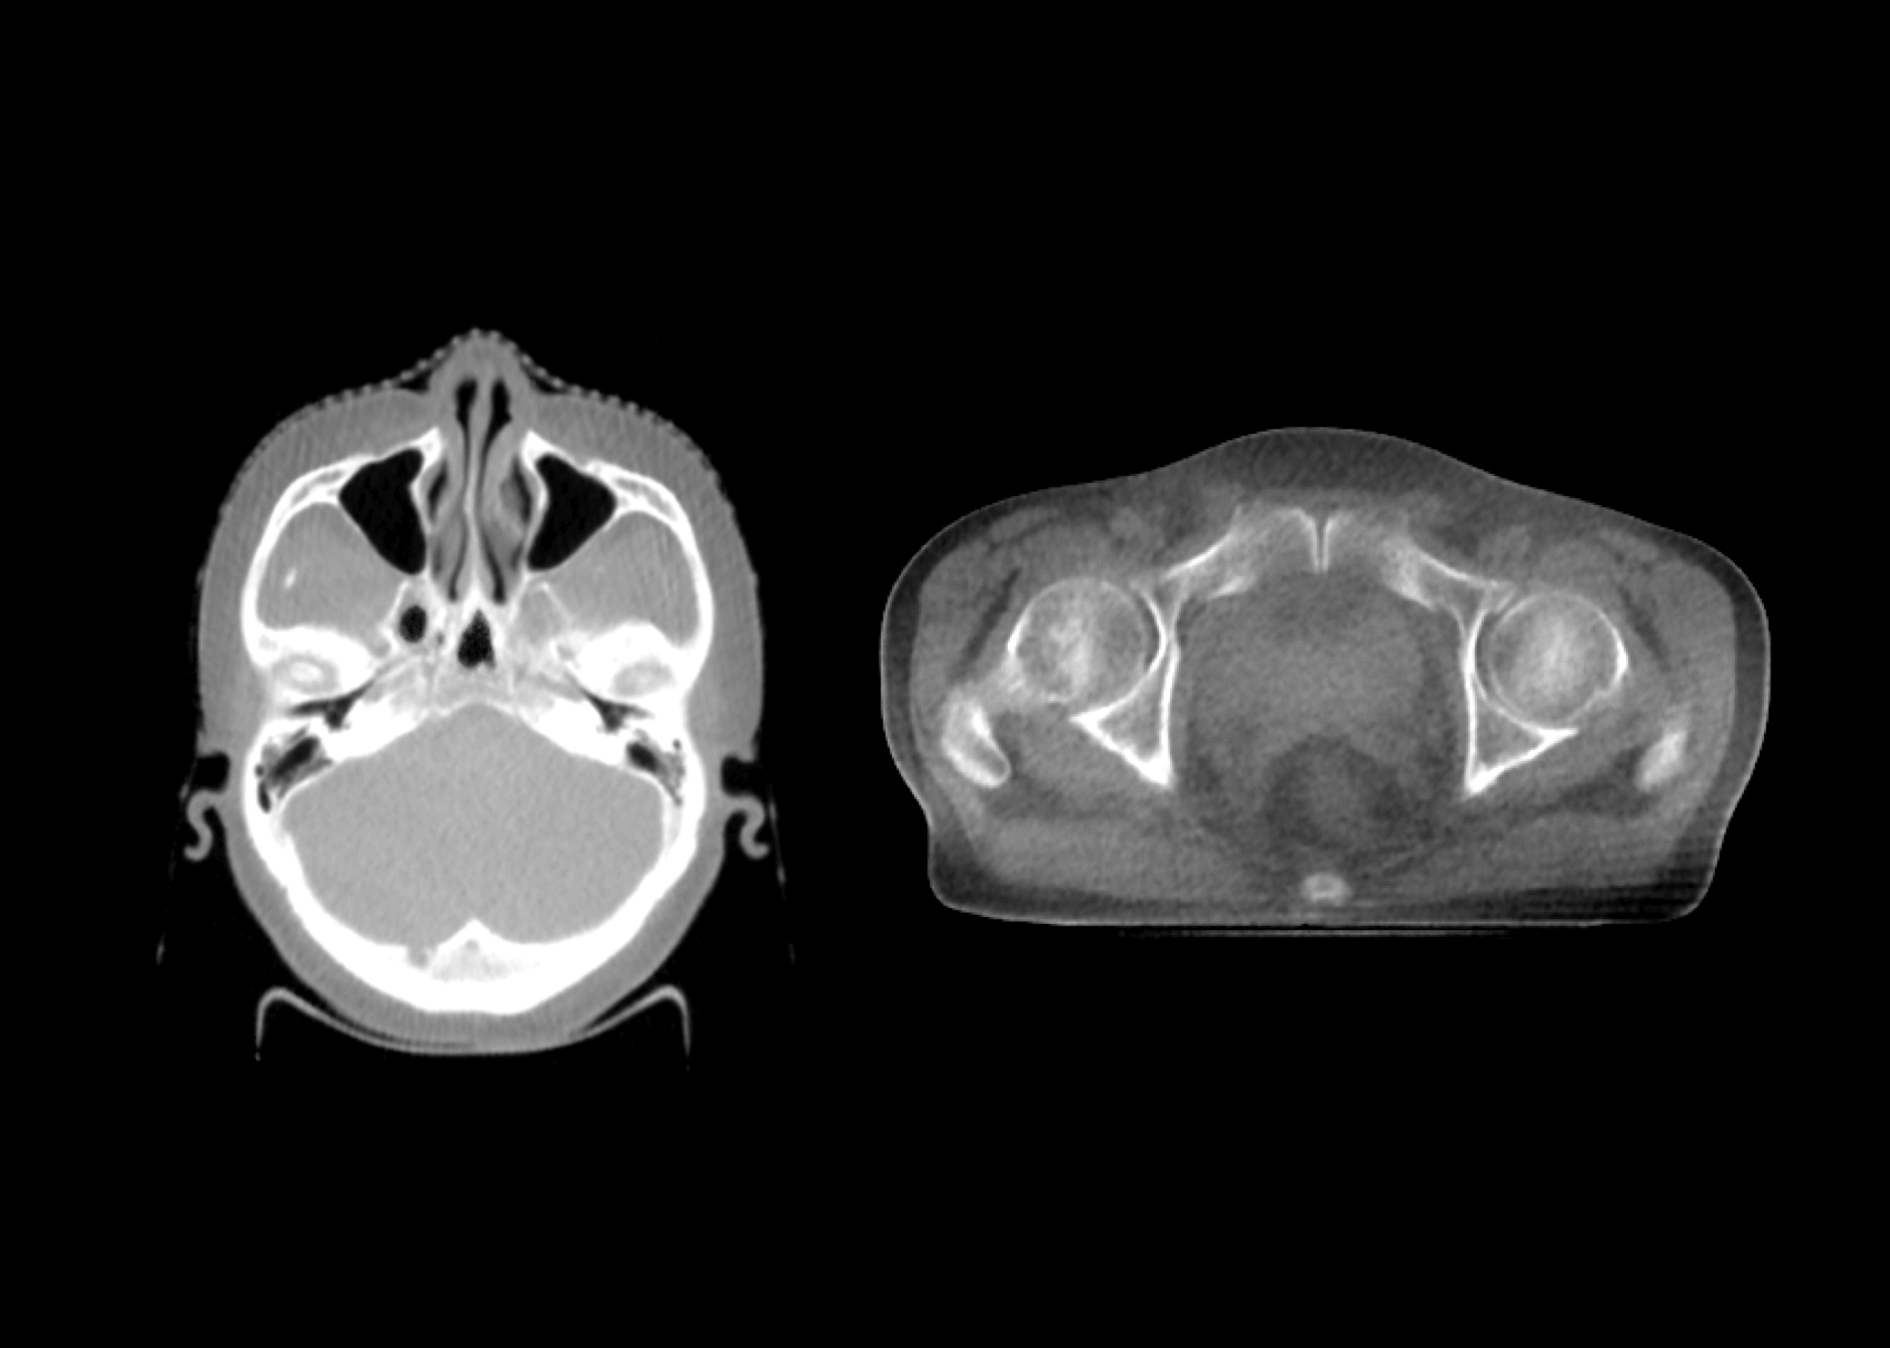

1.5MeV电子束打靶,使得千伏级成像光子占比更大,图像质量媲美常规kV级CBCT。

影像引导成像束流与治疗束流同一等中心,带来更高的图像引导精度。